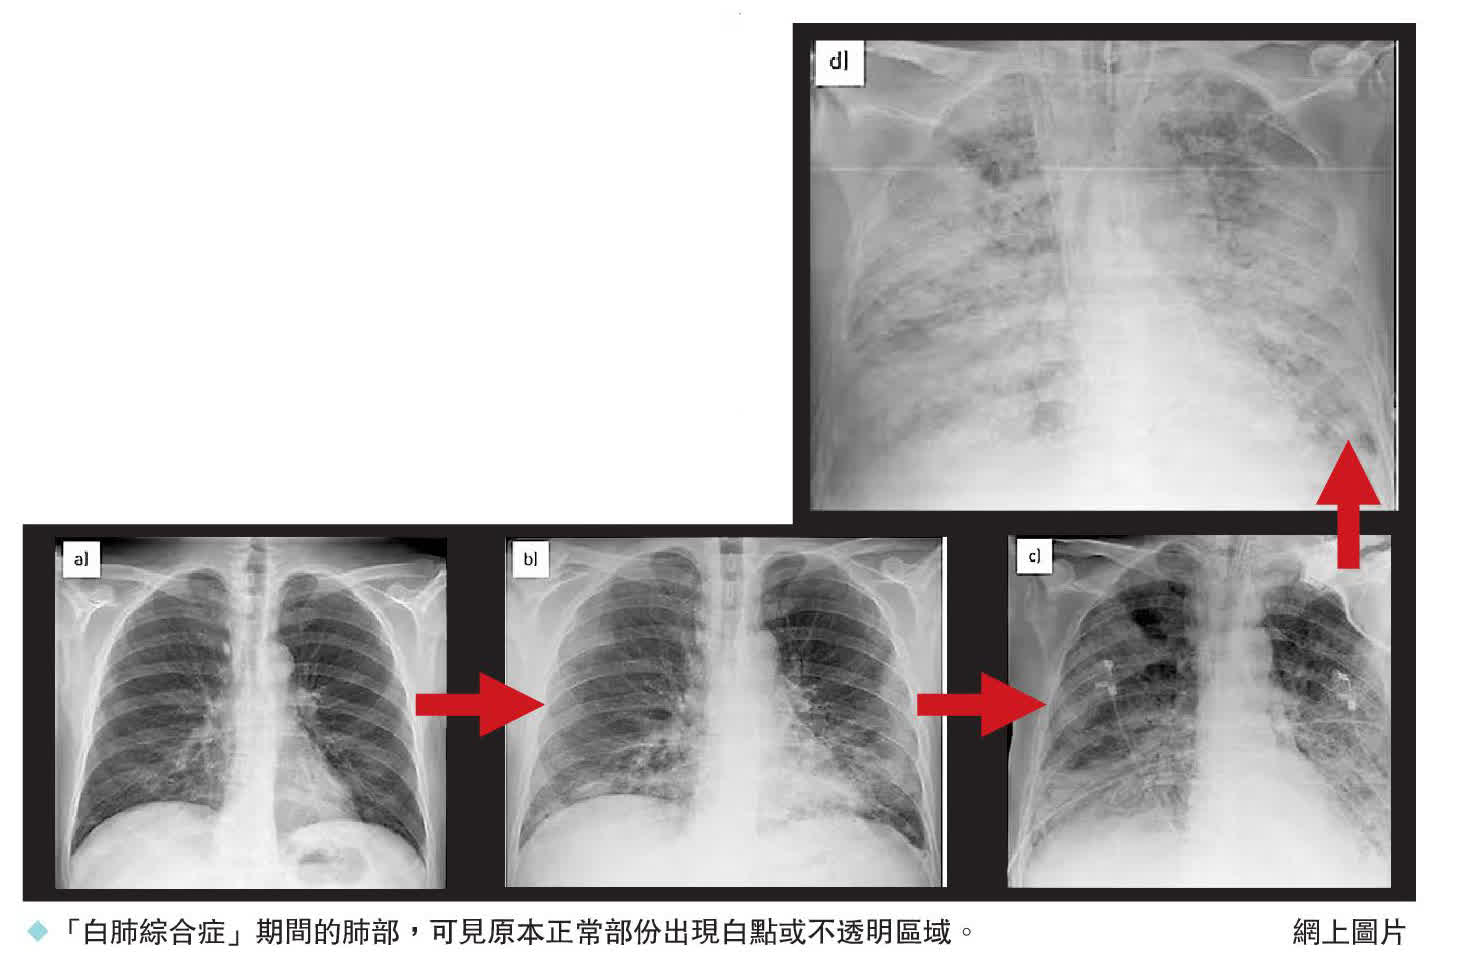

據悉這些在歐洲國家流行的肺炎病症相對較為溫和,患者的肺部在X光片會呈現白色。丹麥血清研究所警告說,預計這種肺炎的病例會在冬天持續增加。